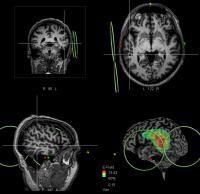

Patient's Real-Time MRI (IMAGE)

For the first time, scientists have precisely identified and targeted an area of the brain which is involved in 'hearing voices', experienced by many patients with schizophrenia. They have been able to show in a controlled trial that targeting this area with magnetic pulses can improve the condition in some patients.